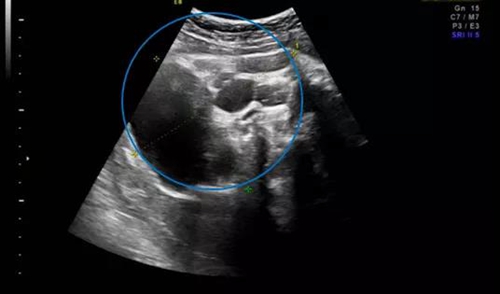

幾個(gè)月前,家住外地的準(zhǔn)媽媽唐女士(化名)在當(dāng)?shù)蒯t(yī)院產(chǎn)檢時(shí),超聲發(fā)現(xiàn)肚里的寶寶患有骶尾部畸胎瘤,直徑達(dá)5厘米,近乎胎兒頭顱大小,當(dāng)?shù)蒯t(yī)院建議終止妊娠?!岸シ砰_(kāi)以來(lái),我和我老公就一直想再要個(gè)孩子,好不容易懷上了,我們真舍不得?!碧婆空f(shuō)道。抱著試試看的想法,唐女士被轉(zhuǎn)診到青島婦兒醫(yī)院胎兒醫(yī)學(xué)門(mén)診。

在聽(tīng)到專家們專業(yè)全面的咨詢后,唐女士決定積極配合治療。后期體檢中,寶寶的畸胎瘤逐漸增長(zhǎng),分娩前最后一次超聲提示畸胎瘤直徑達(dá)10cm,但并未出現(xiàn)羊水過(guò)多等異常情況。